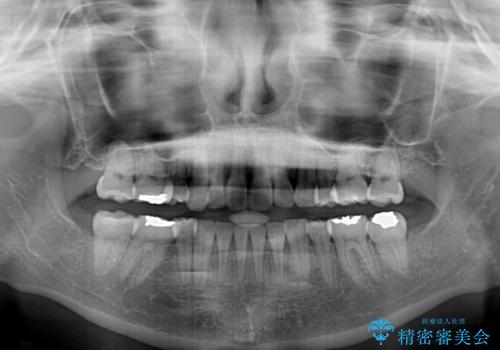

デコボコで飛び出した前歯 ワイヤー装置による抜歯矯正

口元を積極的に引っ込めるために、上下左右の小臼歯計4本を抜歯することとしました。

矯正治療前の咬み合わせで、前歯がすり減ってしまい、歯列が整ったときに先端がガタガタになってしまったため、矯正治療後に形態修正を行いました。